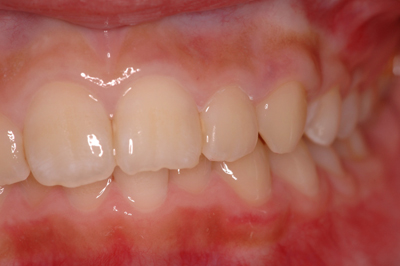

矯正治療例

施術前

施術中

施術後